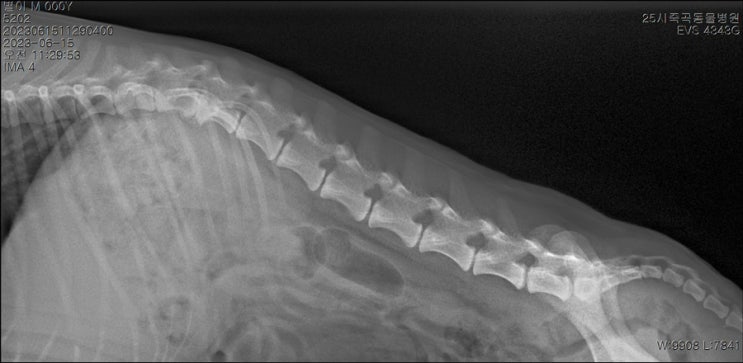

강아지 허리디스크 증상 및 검사 후기 1 (검사 결과 및 비용)

안녕하세요. Z ㅣ수입니다. 오늘은 제 가족이자, 반려견인 별이 이야기를 조금 해보려고 해요. 강아지 허...